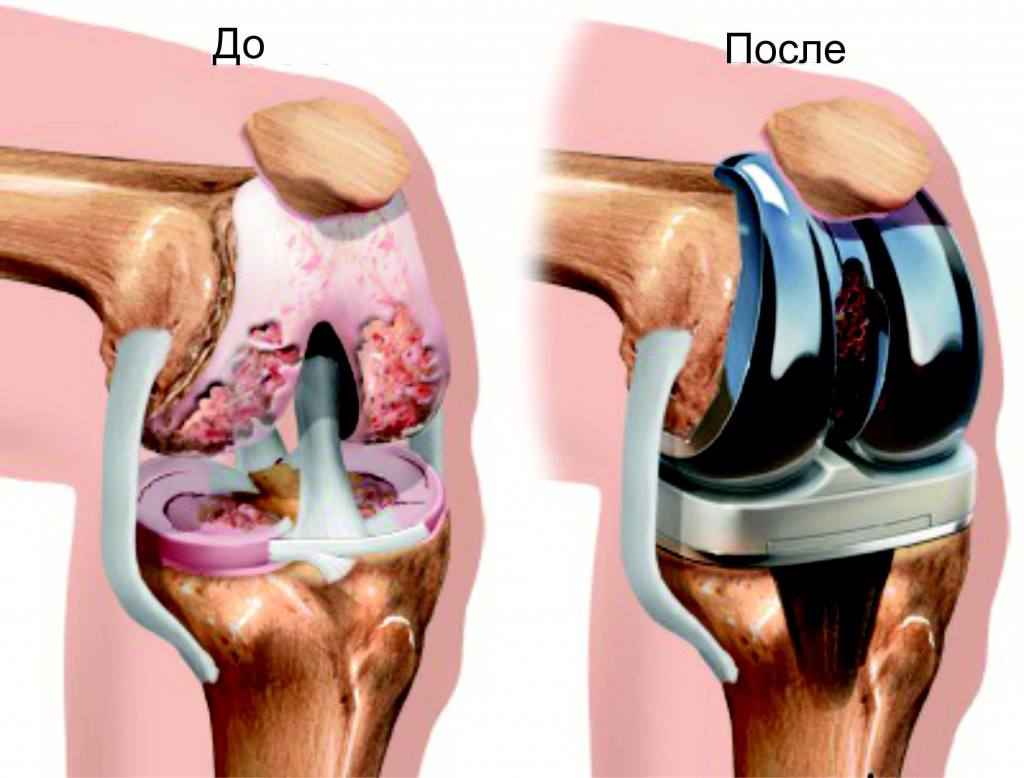

Endoprotezlash

Zararlanган bo'g'imlarni sun'iy protez bilan almashtirish

Knee replacement

Tiz bo'g'imini protezlash

Zararlanган tiz bo'g'imini sun'iy protez bilan almashtirish operatsiyasi. Zamonaviy titanium implantlar uzoq xizmat muddatini va to'liq harakat erkinligini ta'minlaydi.